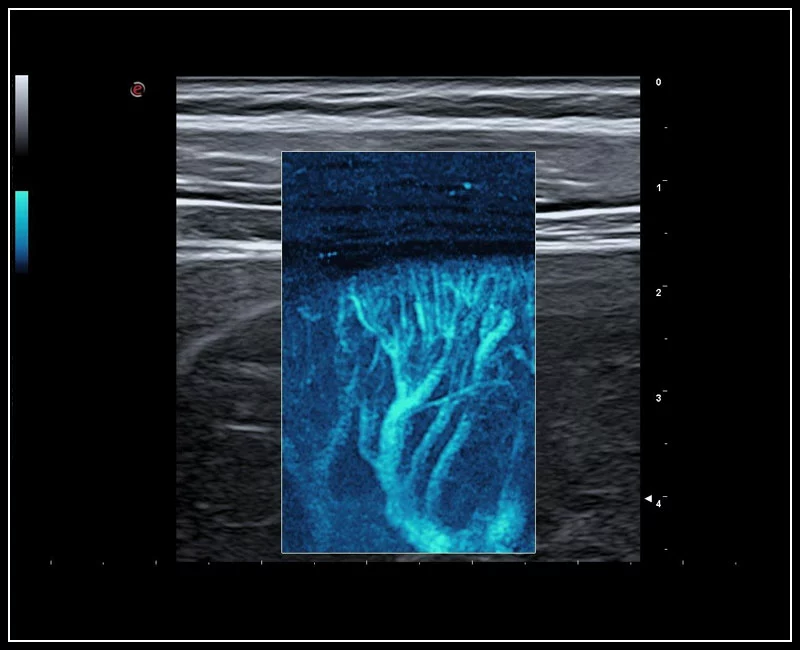

MyLab™C30 - MICROV-NEW

MyLab™C30 - MICROV-NEW

MyLab™C25 - MICRO-V-thyroid-linear

MyLab™C25 - MICRO-V-thyroid-linear

MyLab™E80 - microV - Thyroid

MyLab™E80 - microV - Thyroid

MyLab™9 Platform - Advanced hemodynamic analysis in thyroid nodule with microV

MyLab™9 Platform - Advanced hemodynamic analysis in thyroid nodule with microV

MyLab™9 Platform - Very-superficial linear imaging with Power Doppler algorithm

MyLab™9 Platform - Very-superficial linear imaging with Power Doppler algorithm